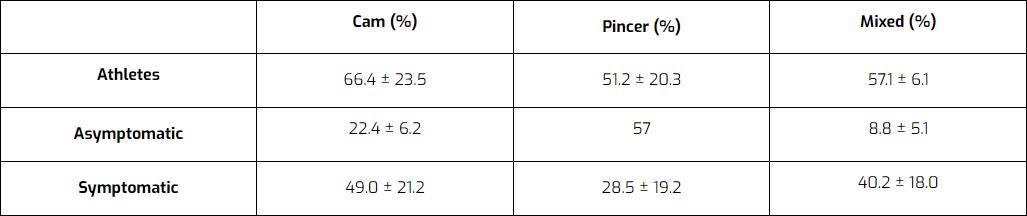

このような形態は、思春期に要求される特異的な適応として発達することが示唆されている。 成長板がずれることで、頭部が丸くならず、大きくなるのかもしれない。 成長板が閉じると、もう形態は変わらない。 FAIの形態は無症状の人によく見られ、アスリートの50~70%にも見られる。 つまり、多くの人に異常があるが、痛みを発症するのはごく一部なのだ。

によるレビュー マスカレンハスら (2016)は、運動選手、無症状者、有症状者におけるカム型、挟み型、混合型FAIのいずれかの形態を持つ患者の割合を示している。 その結果である: